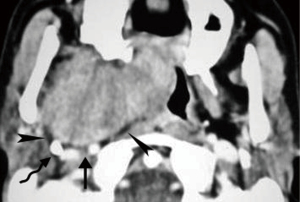

Schwannomas are benign tumors arising from Schwann cells surrounding peripheral nerves. Schwannomas in the carotid space most commonly stem from the vagus nerve. The tumor is usually a sharply demarcated round or oval mass with hypo-, iso-, or hyper-attenuation. Cystic degeneration, xanthomatous change, or areas of relative hypocellularity adjacent to densely cellular or collagenous regions usually contribute to heterogeneity of the tumor (Figure 1) (9,10). Schwannomas are hypovascular tumors, but in dynamic scans, they can show marked enhancement due to pooling of contrast agent resulting from poor venous drainage (11). More often, schwannomas demonstrate a variable degree of enhancement, most commonly patchy enhancement (Figures 2-7).

Due to its location between the vein and artery in the carotid space, schwannomas of the vagus nerve tend to separate the artery and vein, usually displacing the CCA/ICA medially and the IJV laterally (Figures 2,3) (12). Some schwannomas of the vagus nerve may displace the IJV and ICA/CCA in a posterior direction without splaying them and there is usually separation between the artery and vein (Figure 4). The cervical sympathetic chain runs in a fascial reflection posterior and slightly medial to the carotid space. Hence, schwannomas of the sympathetic chain tend to displace the IJV and CCA/ICA together, usually anteriorly and laterally (Figure 5) (5). A large schwannoma of the sympathetic chain may distort the surrounding anatomy and result in a posterior displacement of the carotid vessels without separation of the artery and vein (Figure 6) (13,14). Occasionally, a schwannoma of the cervical sympathetic chain may splay the internal and external carotid arteries at the carotid bifurcation but without encasing the arteries (Figure 7) (5). In these regards, the position of the tumor relating to the vessels in the carotid space is more important than the direction of vascular displacement. There has also been a reported case of schwannoma arising from the glossopharyngeal nerve in the carotid space causing posterior displacement of the ICA (15).